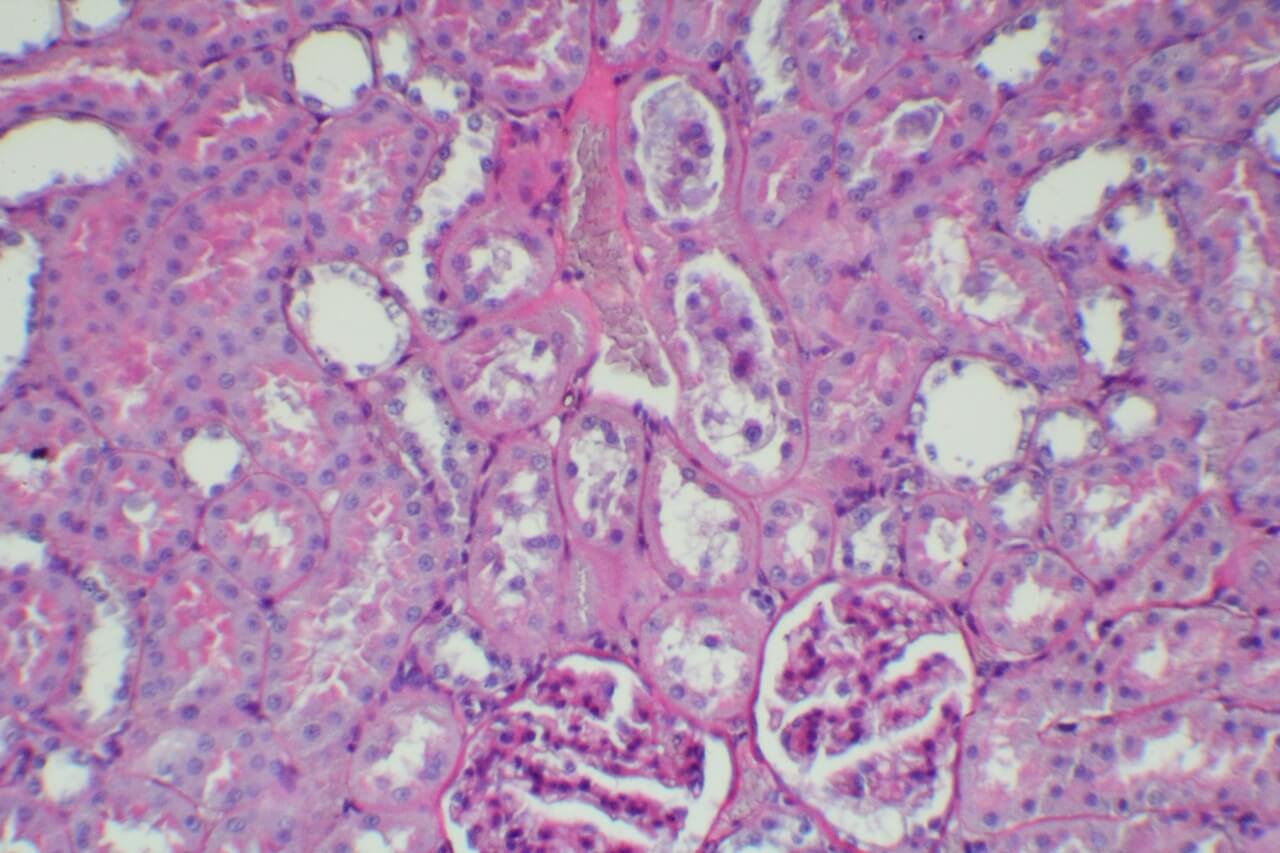

HE染色

By

立众小編1號

2021-07-01